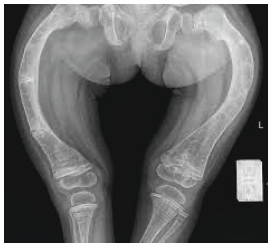

A 6-year-old boy is brought to the physician for a well-child examination. His mother has noticed he frequently falls while running. He was born at term and pregnancy was uncomplicated. He has a seizure disorder treated with phenytoin. He is at the 20th percentile for height and at 30th percentile for weight. Vital signs are within normal limits. Examination shows decreased muscle strength in the lower extremities. There is a deep groove below the costal margins bilaterally. An x-ray of the lower extremities is shown. Which of the following is the most likely cause of these findings?